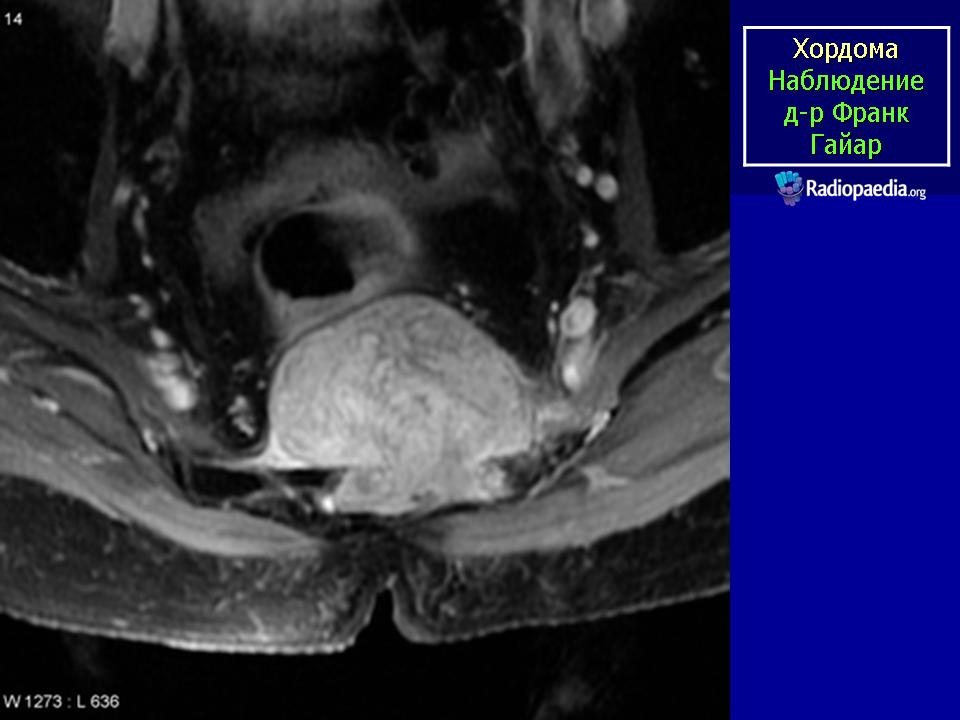

МР-изображения показывают большую гетерогенную твердую разрушающую массу, включающую большинство крестца и копчика, характерные для хордомы

Хордома крестца.

Случай 2: sacrococcygeal

Случай 10: sacrococcygeal

Случай 12: sacrococcygeal

Случай 15: рецидивирующий sacrococcygeal